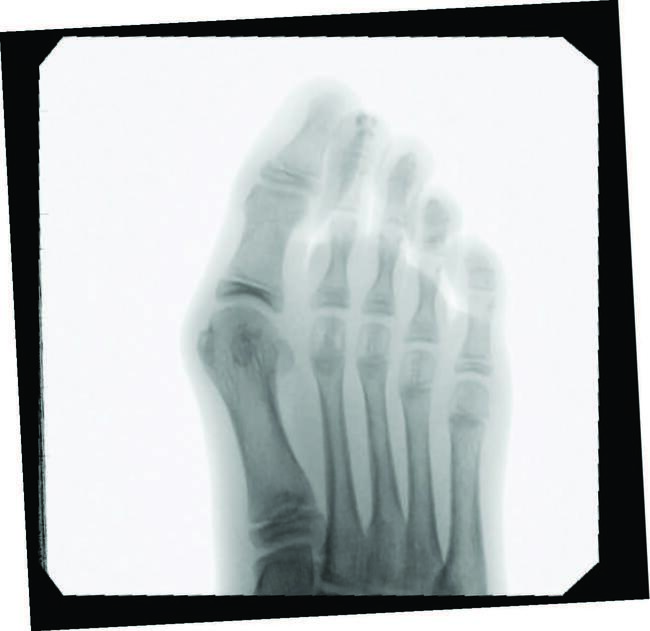

Minimally Invasive Approaches To Juvenile Hallux Abducto Valgus Deformity

Juvenile hallux abducto valgus (HAV) deformities affect approximately 36 percent of the pediatric population, predominately female.1 One can attribute juvenile HAV deformity to congenital, neurogenic, idiopathic etiologies, and/or biomechanical compensatory changes.1 During the physical exam, one must examine and rule out congenital deformities to accurately determine the best treatment options. It is also important to consider the neuromuscular influences of cerebral palsy and myotonic dystrophy, as well as joint laxity-associated disorders like Marfan and Ehlers-Danlos syndromes.2 Though pain and function help drive a provider’s decision-making process, parental concerns with difficulty finding adolescent shoes to accommodate the HAV must also be a consideration in the treatment decision-making process.

Predictors of juvenile HAV severity, in addition to subtalar joint pronation, include: rounding of the first metatarsal head; an atavistic cuneiform; a hypermobile or long first ray; and a high metatarsus primus adductus angle.4 Additional pes planus-related radiographic measurements include an increased first intermetatarsal angle, reported in 26.6 percent of adolescents and an increased metatarsus primus varus angle in 8.1 percent.5 Anatomic abnormalities such as Achilles equinus contractures, digital contractures, syndactyly, metatarsus adductus, hereditary exostoses, and congenital hip dislocation may need attention for long-term successful HAV treatment. Other considerations include brachymetatarsia, where a shortened lesser metatarsal leads to an abnormal transverse metatarsal parabola, allowing more lateral deviation of the hallux and increased metatarsus varus angle due to soft tissue balancing effects.

Harb and team reviewed patient satisfaction and radiological outcomes of more traditional methods of juvenile HAV correction, including proximal metatarsal, shaft, and distal procedures from nine different studies.1 Complications included infection (two percent), postoperative pain (11.9 percent), recurrence (eight percent), non-union (0.5 percent), metatarsalgia (0.5 percent), scar hypersensitivity (4.5 percent), and development of complex regional pain syndrome (0.5 percent). The overall revision rate was four percent due to non-union, recurrence, and dissatisfaction with cosmesis.1 One study also focused on the MIS approach, which reported undercorrection (10 percent). The review concluded that as fixation methods and techniques improve in surgical correction of juvenile HAV, patient satisfaction and clinical outcomes will only continue to improve. Also, they noted that anatomic variations influenced by skeletal maturity continues to influence surgical timing.1